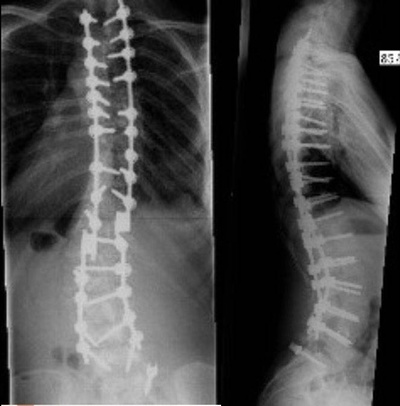

Автор поста оценил этот комментарий

Единственный способ надёжно стабилизировать позвоночник, насколько мне известно, представлен на снимках

Иллюстрация к комментарию

Сама конструкция не гнется. Подвижность может остаться в крестцовом отделе. Самостоятельно обуться она позволяет. Приятным бонусом идёт идеальная осанка